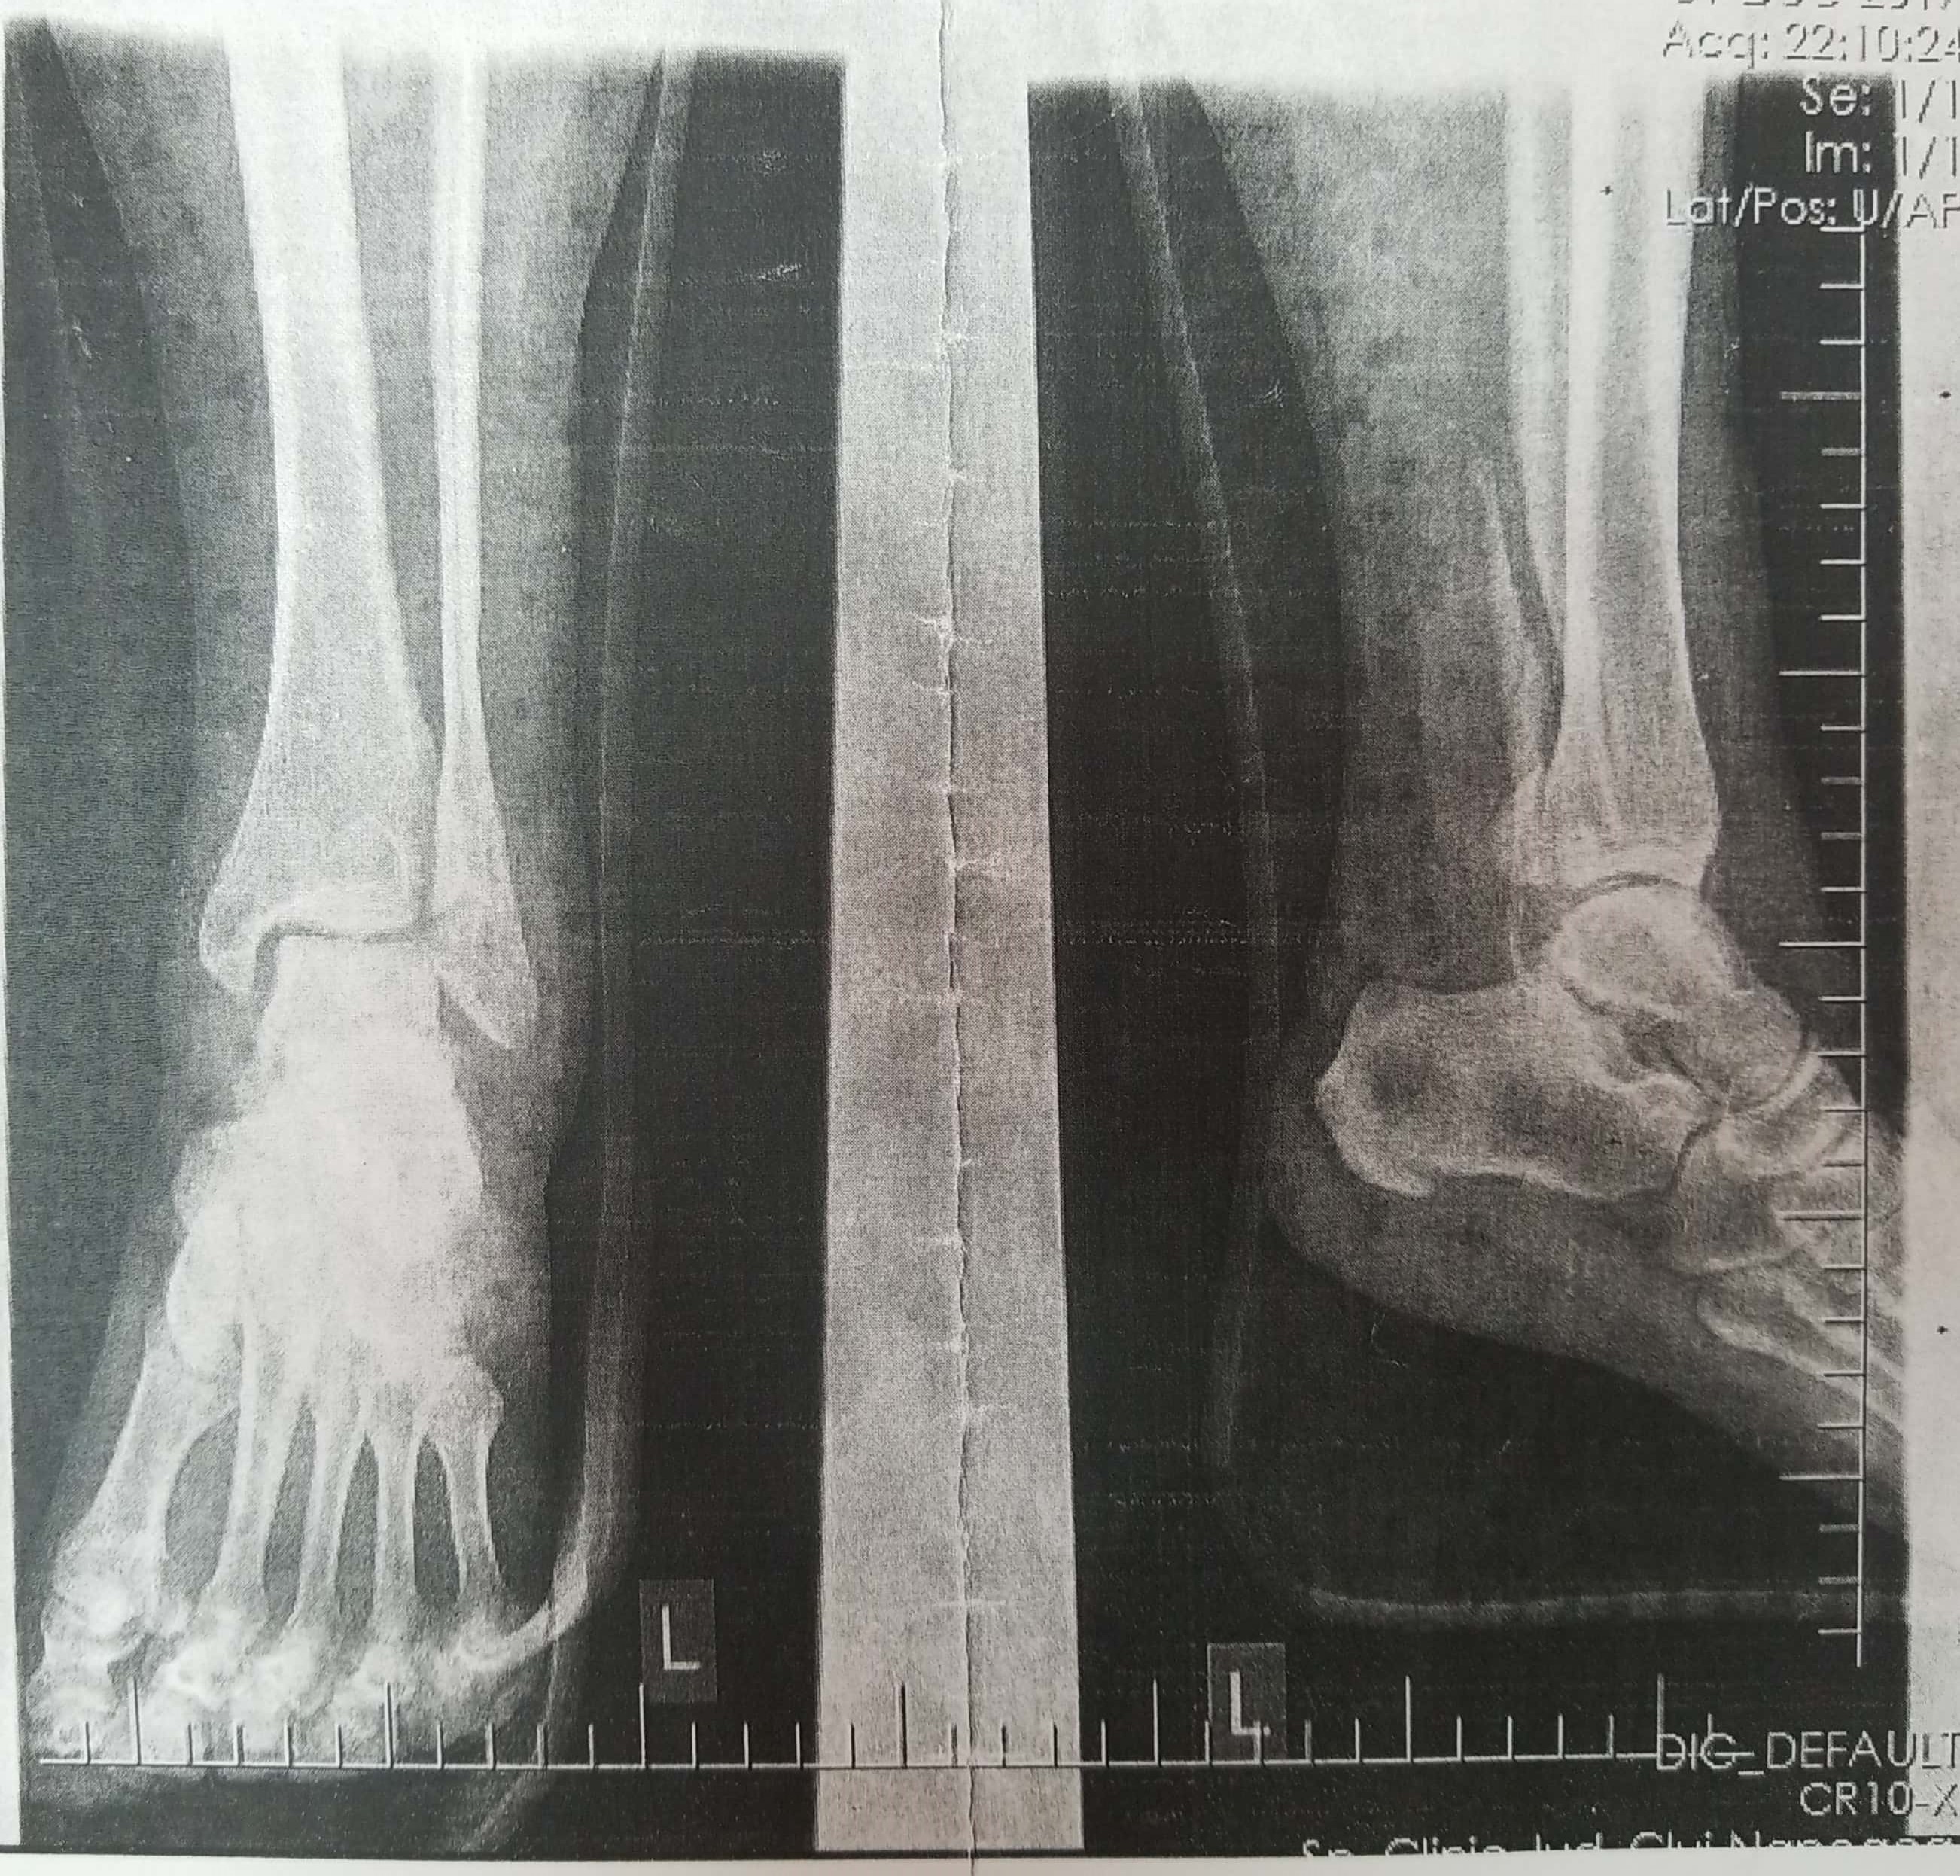

FRACTURA TRIMALEOLARA STANGA